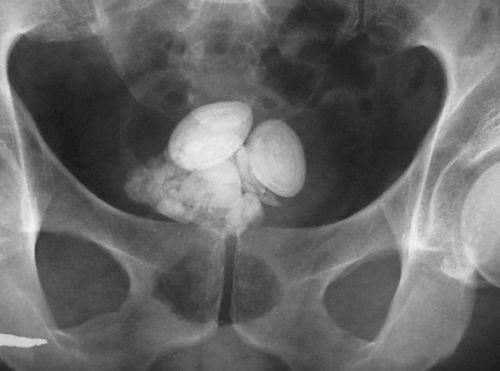

Обзорная рентгенография

Рентгенография обзорного типа выполняется горизонтально и вертикально, что полезно для диагностики холецистита при желчекаменной болезни. Камни черного цвета содержать достаточно кальция, чтобы отображаться на рентгене. Воздух в протоках указывает на наличие свищей, а если при этом стенки кальцифицированы, то это симптом хронической формы патологии. Выполняется обзорная рентгенография при подозрении на желчекаменную болезнь, при сомнительных острых болях в животе.

Черный цвет конкремента обозначает билирубиновый состав, что часто встречается при циррозе печени или продолжительном гемолизе. По консистенции они мягкие, но если подсоединяются соли кальция, то образование заметно на рентгене с контрастом. У детей эти камни встречаются в половине всех случаев.